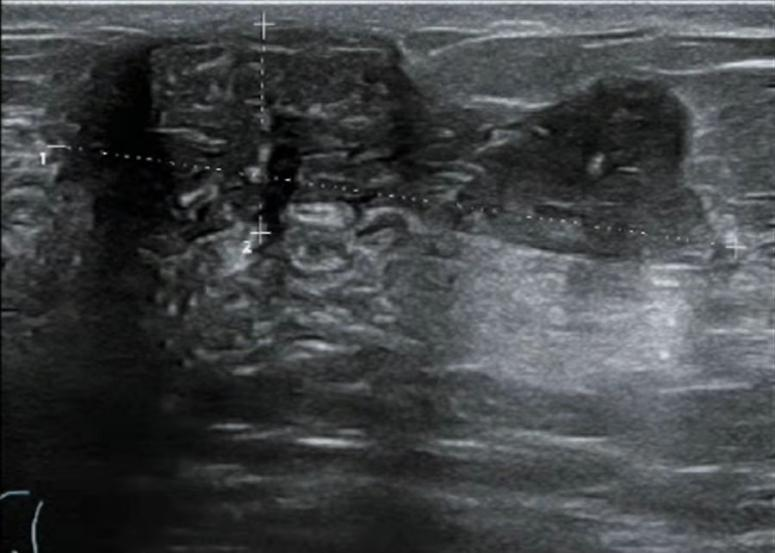

2021.7.7乳腺MRI:右乳外上象限肿物(BI-RADS-6)3.1cm×1.9cm×3.0cm,右腋窝见肿大淋巴结,M灶可能。

右乳外上象限见不规则肿块,呈长/稍长T2、等T1信号,DWI呈高信号,ADC图信号减低,ADC值约0.863,增强扫描明显强化,TIC呈Ⅲ型,大小约3.1×1.9×3.0cm,邻近皮肤增厚,皮下脂肪层模糊,另肿块外侧旁见小肿块影,增强明显强化,与外上象限肿块相连。右侧腋窝见肿大淋巴结。

图3. 乳腺MRI

(3 cycle 后)2021.9.22 复查乳腺MRI示:右乳肿块较前减小14mm×9mm×18mm。

图7. 乳腺MRI